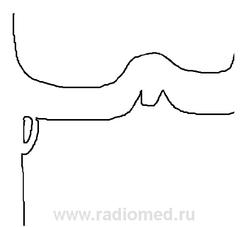

Извиняюсь за качество рентгенограммы и ее фото (в отражении мои руки с фотоаппаратом), поэтому нарисовал схему, как я вижу рентгенологическую картину. Это авульсионный перелом, или рассекающий остеохондрит\оз, или третье (ваш вариант)? Есть рентгенограмма в боковой проекции, но она тоже плохого качества, при необходимости выложу.

Контуры костных фрагментов гладкие, чёткие.Впечатление, что отделившийся фрагмент более плотный, чем основная кость. Думаю, какая-то остеохондропатия (остеохондрит?).

Отрыв коркового слоя внутреннего мыщелка большой берцовой кости с минимальным смещением. Посоветоваться с травматологом (частичное повреждение внутренней боковой связки) по поводу направления на МРТ.

Сначала чуть улучшу, но не намного. Потому что снимок изначально дефектный. Таких сейчас много. Можете не слушать, но не бывает такого неожиданного (пускай, травматического) правильного рассечения без смещения и плотности тканей изменения...

(Два прямых - снимки на разном режиме - не помогло скрыться, остеопороз отлично на каждом из них виден.)